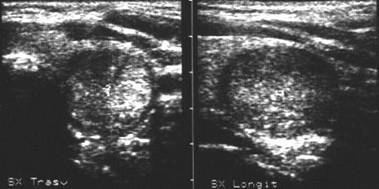

Lob drept, proiectie trasversale si longitudinala.

Femeie de 23 ani. Sub capsula, un mic nodul, de 12x16x19mm (1,8 cc), hipoecogen, neomogen, cu margini ne definite. Examen citologic prin citoaspiratie: carcinom papilar confirmat si histologic.